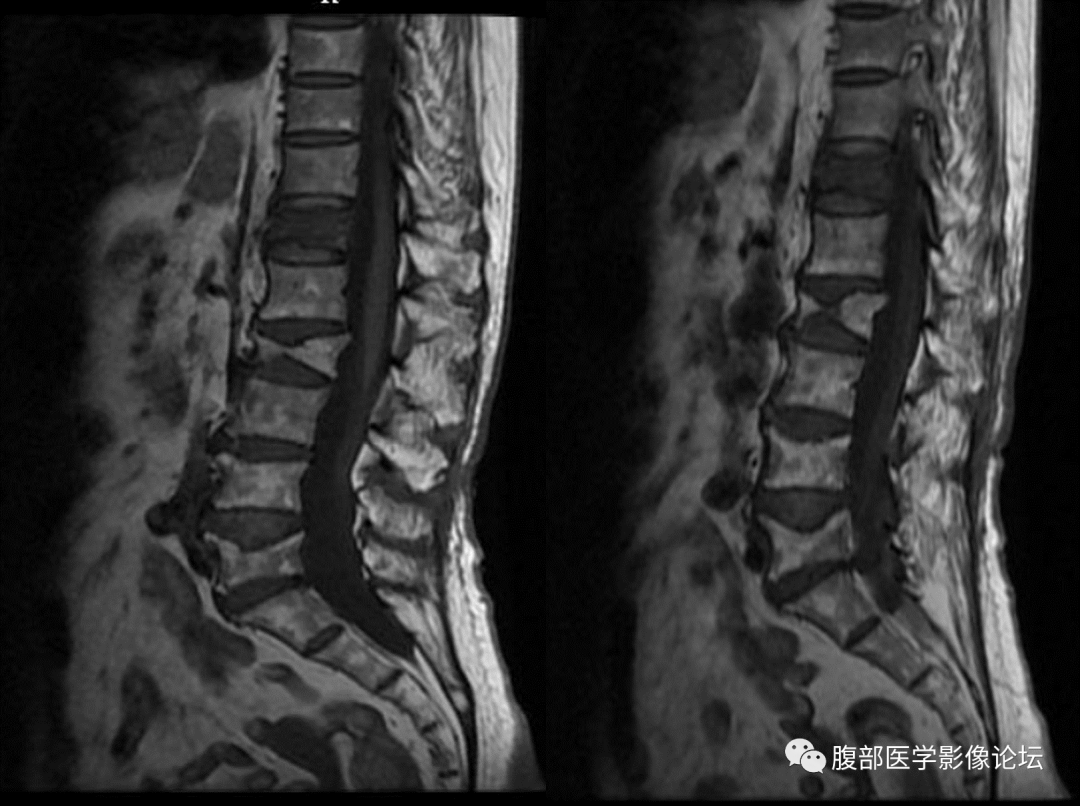

3、椎体内积液或积气

良性骨折征象,恶性骨折无此征象

4、椎体终板下低信号带

良性骨折有此征象(骨折线及周围挫伤、水肿),恶性骨折无此征象

5、椎体后缘骨皮质形态

良性骨折:椎体后缘骨皮质形态连续完整,保持轻度前凹样的凹镜型

恶性骨折:椎体后缘骨皮质中断不完整,后缘向后凸的凸镜型